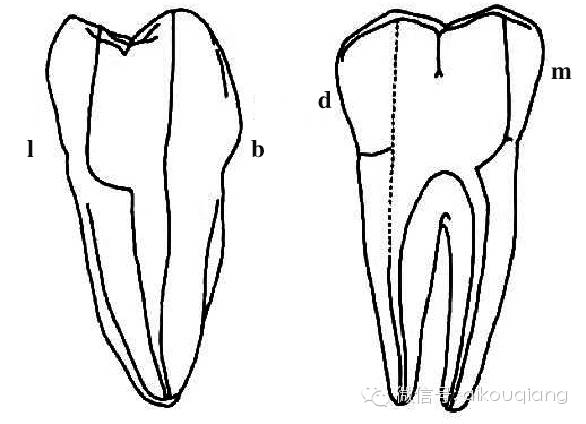

crown-down技术要求冠部髓腔预备完成后器械可以直线进入根管,高速球钻这时简直是捣乱。尤其我一直采用的是“平面开髓”见下图:

口腔H锉怎么消毒根管治疗器械的选择_https://www.jmylbn.com_新闻资讯_第4张

图 平面开髓1

口腔H锉怎么消毒根管治疗器械的选择_https://www.jmylbn.com_新闻资讯_第5张

图 平面开髓2

关于“平面开髓”:注意到开髓的时候不是一个“点”,而是一个平面,这个平面略小于髓腔,在髓腔的正上方,在开髓的时候是一层一层深入的,这种方法的好处:1、随时可以观察到露髓点,2、即使是增龄性变化很大的牙齿,也不会损伤到髓室底。缺点是:需要对髓腔形态烂熟于心中,要不然有时会过多破坏牙体,说到这个其实不是问题,要想做一个合格的牙体牙髓大夫,这是必要条件。那么你想想,球钻能弄好“平面开髓”吗?